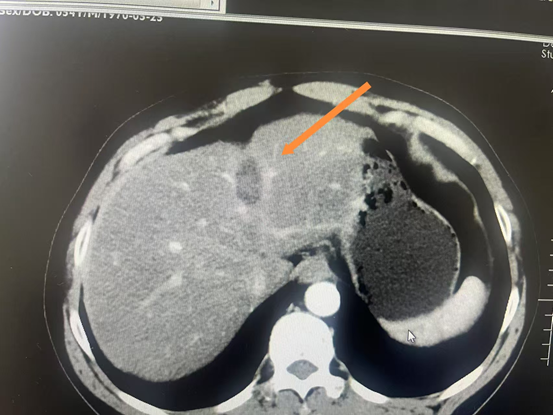

7. 肝脏肿瘤射频消融

B超定位射频消融治疗小肝癌